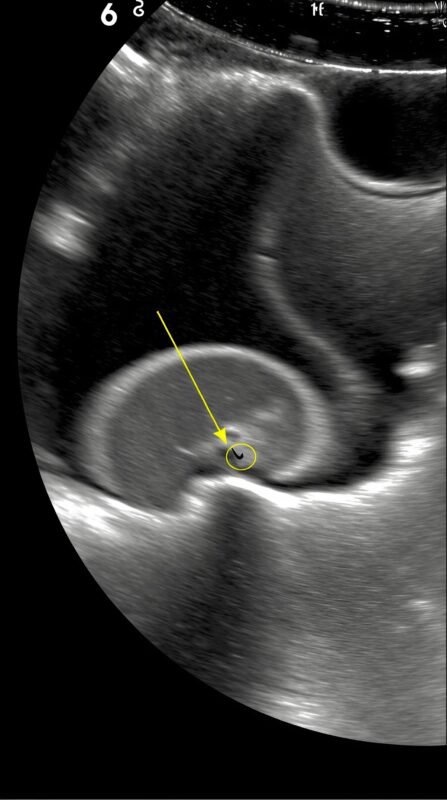

Seeing my panic, he explained gently. The scan showed something small but dangerous inside her stomach. Something sharp. Something that didn’t belong there.

A pin.

My four-year-old daughter had swallowed a pin.

The doctor didn’t waste time. Pins can move, puncture, cause internal damage. Every minute mattered .